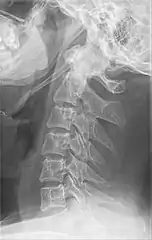

Radiograph, lateral view showing elongated stylohyoid process and stylohyoid ligament ossification

Radiograph, lateral view showing joint-like formation in ossified stylohyoid ligament

Diagnosis is suspected when a patient presents with the symptoms of the classic form of "Eagle syndrome" e.g. unilateral neck pain, sore throat or tinnitus. Sometimes the tip of the styloid process is palpable in the back of the throat. The diagnosis of the vascular type is more difficult and requires an expert opinion. One should have a high level of suspicion when neurological symptoms occur upon head rotation. Symptoms tend to be worsened on bimanual palpation of the styloid through the tonsillar bed. They may be relieved by infiltration of lidocaine into the tonsillar bed. Because of the proximity of several large vascular structures in this area this procedure should not be considered to be risk free.

Imaging is important and is diagnostic. Visualizing the styloid process on a CT scan with 3D reconstruction is the suggested imaging technique.[12] The enlarged styloid may be visible on an orthopantogram or a lateral soft tissue X ray of the neck.